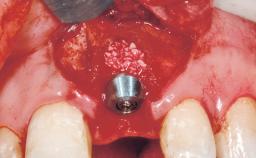

A 30-year-old female patient had lost tooth 21 and was referred to our clinic for consultation and treatment. Due to advanced apical infection, tooth 21 had been extracted two months earlier at another clinic and an acrylic-resin tooth had been bonded to the adjacent teeth. The patient desired implant treatment to avoid any damage to the adjacent natural teeth. While the patient had no history of any systemic disorder, she was a heavy smoker and exhibited medium to advanced periodontitis in the entire jaw. After the initial treatment to achieve a pocket probing depth of less than 4 mm and no bleeding on probing, a decrease in the height of the papillae mesial and distal to the extraction site and overall gingival recession were observed.

Type of Implants One-Piece|Reduced-Diameter

Bone Augmentation Horizontal|Staged

Augmentation Materials Autogenous chips|Membrane